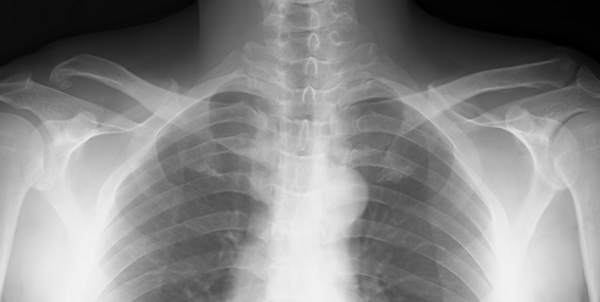

The following X-ray is taken 2 years after the operation.

It is clearly seen that the right acromioclavicular is deformed as it took 20 years since the initial dislocation happened. I only performed to clamp the two joints with autograft ligaments and metal end-buttons as the deformation has been already progressed at the time of surgery.